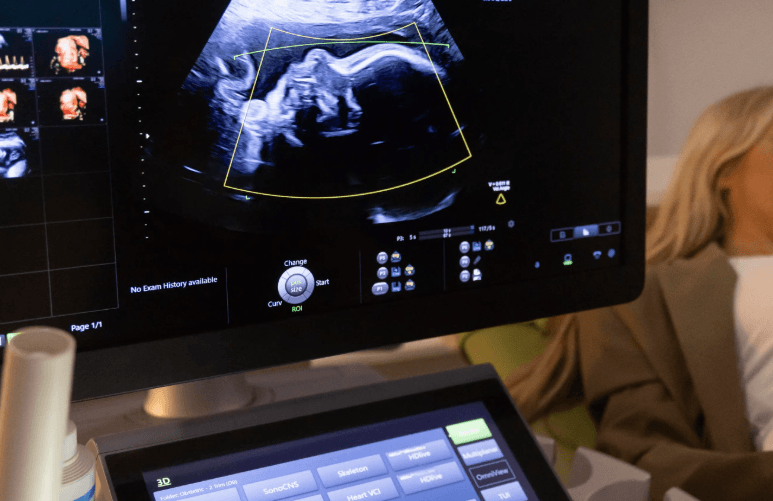

Hamilelik süreci boyunca birçok kez ultrason muayenesine girersiniz ancak "Detaylı Ultrason" (veya halk arasındaki adıyla 2. düzey ultrason), diğerlerinden çok farklıdır. Bu muayene, bebeğinizin sadece boyuna veya kilosuna bakmakla kalmaz; tepeden tırnağa tüm organ gelişimini, plasentanın konumunu ve olası yapısal anomalileri inceleyen bir "check-up" niteliğindedir. Bu tarama süreci, gebeliğinizin en önemli duraklarından biri olduğu için sonuçları mutlaka doktorunuza danışarak değerlendirmelisiniz.

Bu muayene genellikle bir perinatolog (Maternal-Fetal Tıp uzmanı) tarafından yapılır. Uzman, yaklaşık 30 ile 45 dakika süren bu işlemde şu noktaları titizlikle inceler:

Detaylı ultrason sırasındaki o sessizlik bazen ebeveynleri gerebilir ama aslında o sırada içeride muazzam bir belgesel çekiliyor!

Doktorunuz sessizce ekrana odaklanmışken siz "Neden konuşmuyor, bir sorun mu var?" diye ter dökebilirsiniz. Oysa doktorunuz o sırada bebeğinizin böbreğindeki milimetrik bir kanalı veya kalbindeki kapakçığı saymaya çalışıyordur. Bebeğinizin ekrandaki o 3 boyutlu haliyle karşılaştığınızda; burnunun kime benzediğini tartışmadan önce, onun içeride yaptığı o "jimnastik hareketlerini" izlemenin keyfini çıkarın. O sessizlik, aslında bir sanat eserinin incelenme anıdır! 🎥👶🍿